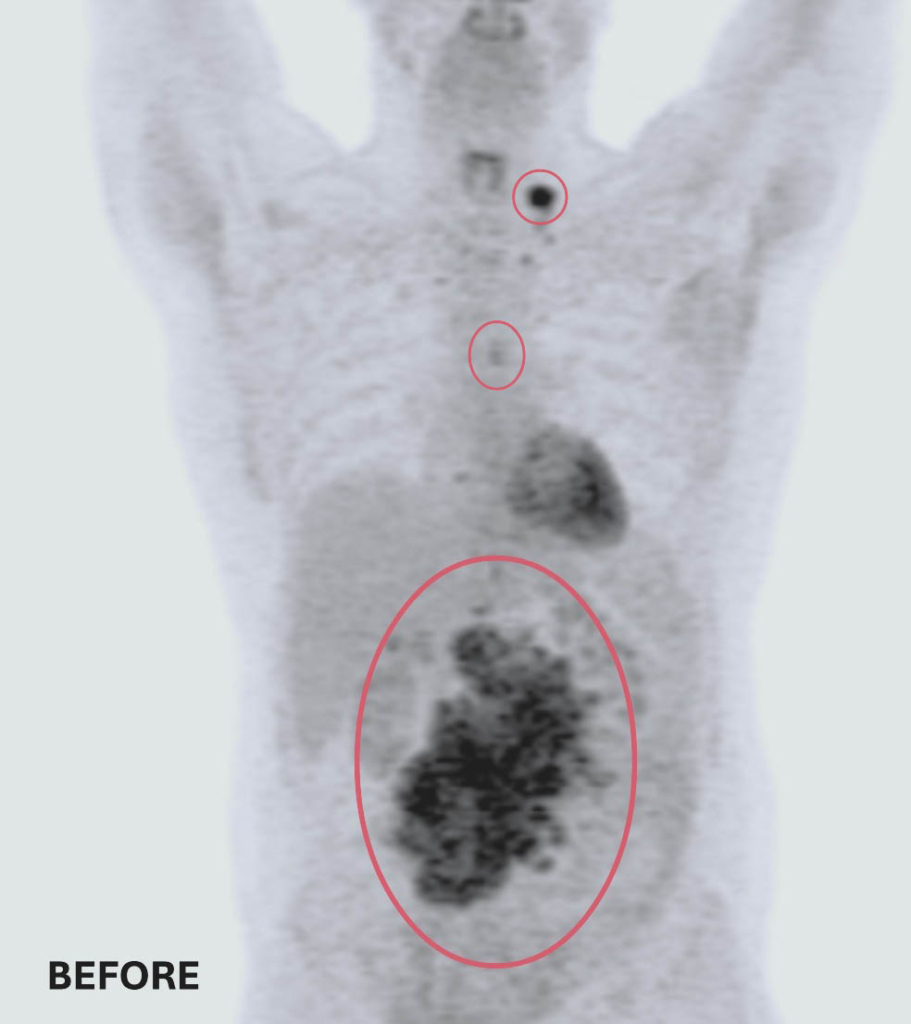

A PET scan revealed three masses. The largest and most concerning mass was in his abdomen and measured 14 by 9 centimetres — roughly the size and shape of an extra-large sweet potato. The other two were located near his esophagus and collarbone.

Before and after treatment scans: Two of Ted’s three tumors completely disappeared. The remaining tumor was reduced to smaller than a pea — a remarkable response to treatment at The Ottawa Hospital.